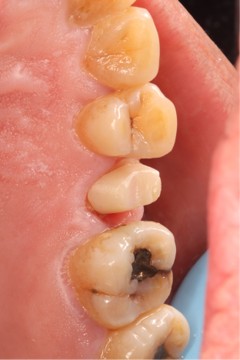

June 20, 2025: The patient's chief complaint is that endodontic treatment was performed on the right maxillary posterior tooth abroad, and a deep carious lesion has been recently detected, requiring restoration. The following are the intraoral photographs taken upon the patient's first visit: a large carious lesion is visible on the occlusal surface of tooth 15 (FDI numbering), with only the buccal wall remaining. Percussion test and cold-hot stimulation test showed no response, and yellow obturation material is visible at the root canal orifices.